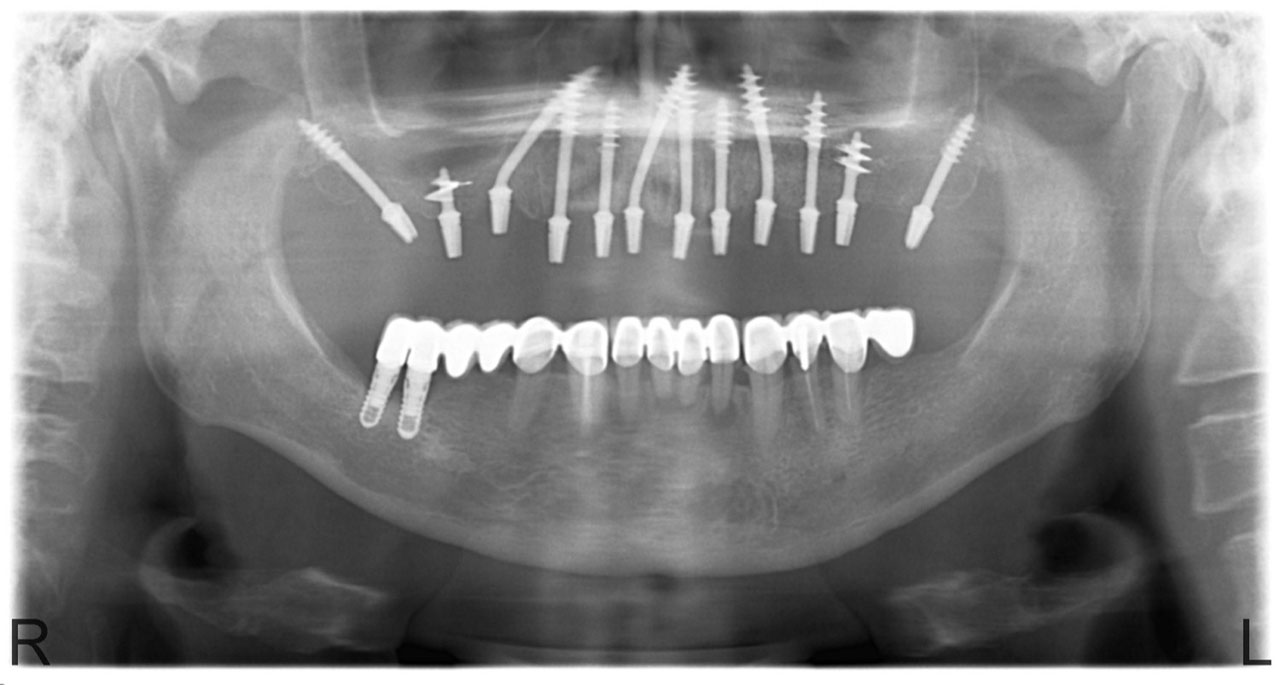

• esettanulmany-01

Implantáció előtt, gyulladt, törött fogak.

• esettanulmany-03

Imlantáció után,bal oldalon már a végleges hidakkal, jobb oldalon még csak az implantátumok.